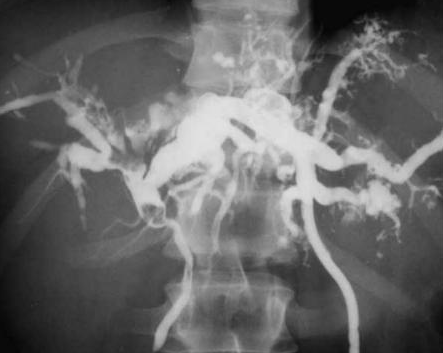

CT Angiography. Presence of a ruptured pseudoaneurysm of the common hepatic artery (Courtesy Dr. V. Penopoulos)